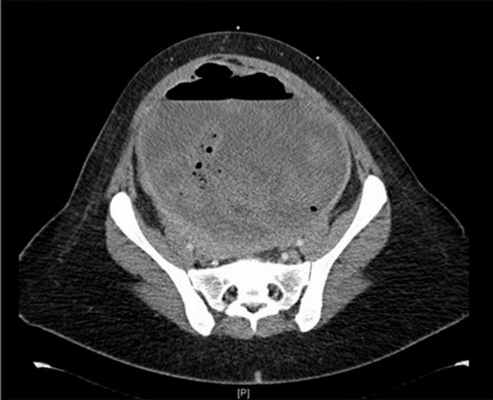

Рис. 7. КТ брюшной полости и таза, демонстрирующая пиомому

УЗИ и экстренная компьютерная томография показала несколько огромных лейомиом матки, самая большая из которых была примерно 8х 9 см, а задняя стенка матки была поражена аденомиозом.

При лапароскопии было обнаружено, что серозный слой над маткой была шероховатый, а рана была обнаружена на задней части шейки матки на уровне внутреннего зева. Была произведена гистерэктомия. Общая кровопотеря составила около 4500 мл.